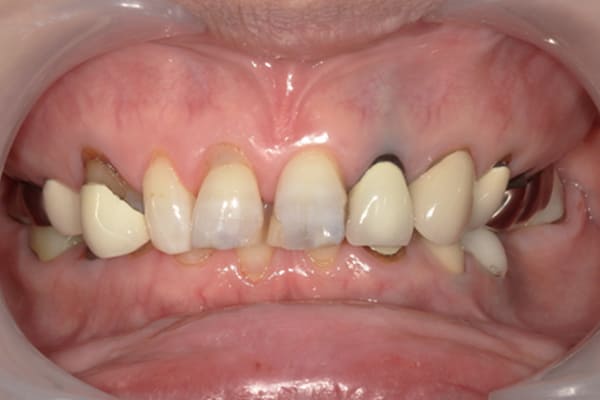

症例レポート[CASE.04]

前歯がとれて痛い、

食事もできず、見た目も悪い

- 性別・年齢

- 女性(60代)

- 主訴

- 前歯がとれて、痛い、食事ができない、見た目が悪く人に会えないので何とかしてほしい

- 治療

-

- 上顎精密金属総入れ歯

- 下顎精密金属部分入れ歯

- 磁性アタッチメント(白金加金) 1歯

- 治療期間

- 約5か月間

- 費用

- 上顎精密金属床総入れ歯:55万円

- 下顎精密金属床部分入れ歯:55万円

- 磁性アタッチメント:11万円×1歯

(白金加金)

合計:121万円(税込)

上前歯はブリッジの差し歯により根が折れ炎症を起こしお痛みのある状態でした。

原因は長期使用により下の義歯の歯が削れたことにより、下前歯が上前歯を突き上げ強い力が加わっていたことが根本的な原因と考えられます。

治療前は、奥歯が下がり、かみ合わせが乱れています。適切な入れ歯はそのままのかみ合わせで義歯を作るのではなく治療後のように、前歯から奥歯までのラインが真っすぐ揃った、かみ合わせの面を適切に付与し、よく咬め、残りの歯に負担がかからないかみ合わせとしました。

とにかく何も食べられないこと、人に会えないことから、なるべく早く何とかしたいとのご希望でした。